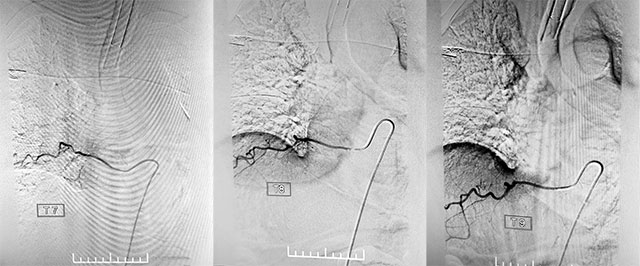

找到病灶只是手術(shù)的第一步,接下來還需要找到具體瘺口,張琪博士團(tuán)隊(duì)采用半椎板入路,硬膜下切開1cm小口,在長(zhǎng)時(shí)間的血流高壓下,顯微鏡下的血管已經(jīng)迂曲增粗,相當(dāng)于要在這個(gè)“面”上找出這個(gè)“點(diǎn)”。張琪博士團(tuán)隊(duì)決定使用一種特殊的材料——美藍(lán)(一種無毒性的染料,它的氧化型呈藍(lán)色,還原型無色),終于成功找到血管畸形點(diǎn)。接下來予以電凝后分離靜脈、切除瘺口。切斷后再次復(fù)查造影,靜脈未再顯影,瘺口順利封閉,手術(shù)成功了。

▲ 復(fù)查造影,靜脈未再顯影,瘺口順利封閉